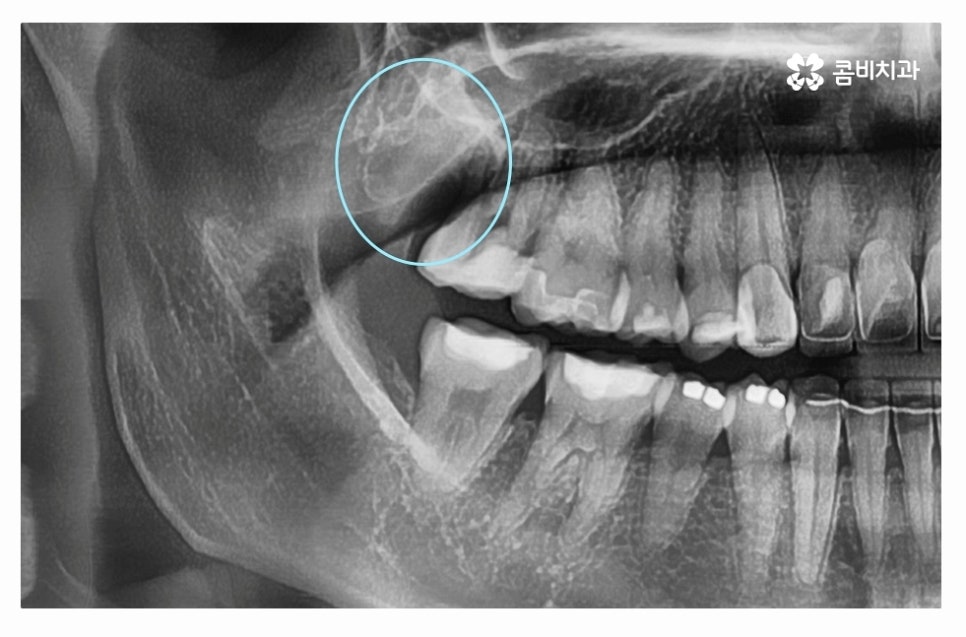

이처럼 잇몸 속에 숨어 있거나 누워서 자라는 사랑니의 경우

사랑니 존재 여부조차 모르다가 검진을 통해서

알게 되는 경우가 많은데 단지 매복되어 있다고 해서

무조건 발치를 해야 하는 것은 아니지만 옆으로 누워서

자라거나 잇몸 아래 매복되어 있는 경우 등에는

잇몸질환을 유발하거나 턱뼈에 낭종을 만드는 경우도 있어요.